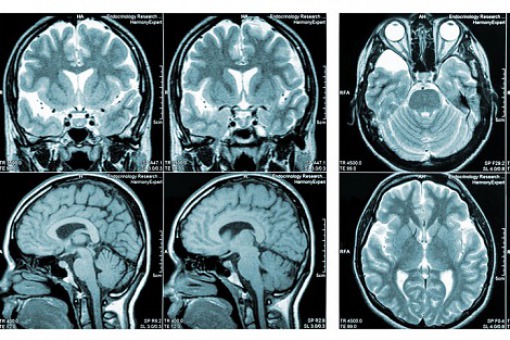

Nowe wytyczne obejmują szeroki zakres tematów związanych z obrazowaniem metodą rezonansu magnetycznego (MRI) w stwardnieniu rozsianym (SM). Nad nowelizacją pracowały trzy międzynarodowe grupy ekspertów.

Nowe wytyczne obejmują szeroki zakres tematów związanych z obrazowaniem, z kluczowymi obszarami zainteresowania. Dotyczą obrazowania rdzenia kręgowego, obrazowania trójwymiarowego (3D), wskazują, kiedy nie należy stosować kontrastu gadolinowego. Poza tym zalecenia odnoszą się m.in. do stosowania rezonansu magnetycznego u pacjentek ze stwardnieniem rozsianym w dzieciństwie, w ciąży oraz w okresie poporodowym. Eksperci omawiają także nowe, obiecujące metody MRI, które mogą w najbliższej przyszłości zasługiwać na wprowadzenie do praktyki klinicznej.